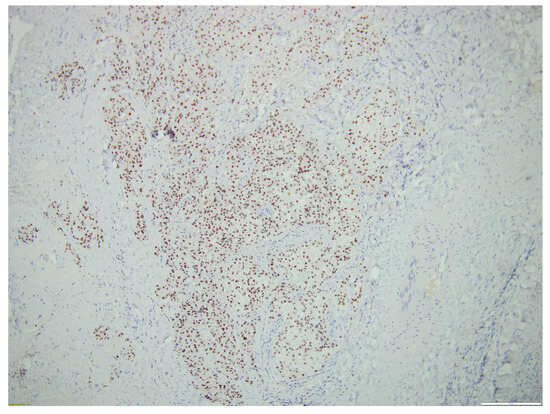

Aggressive Primary Thyroid Mucoepidermoid Carcinoma with Extensive Pulmonary Involvement

2. Case Report